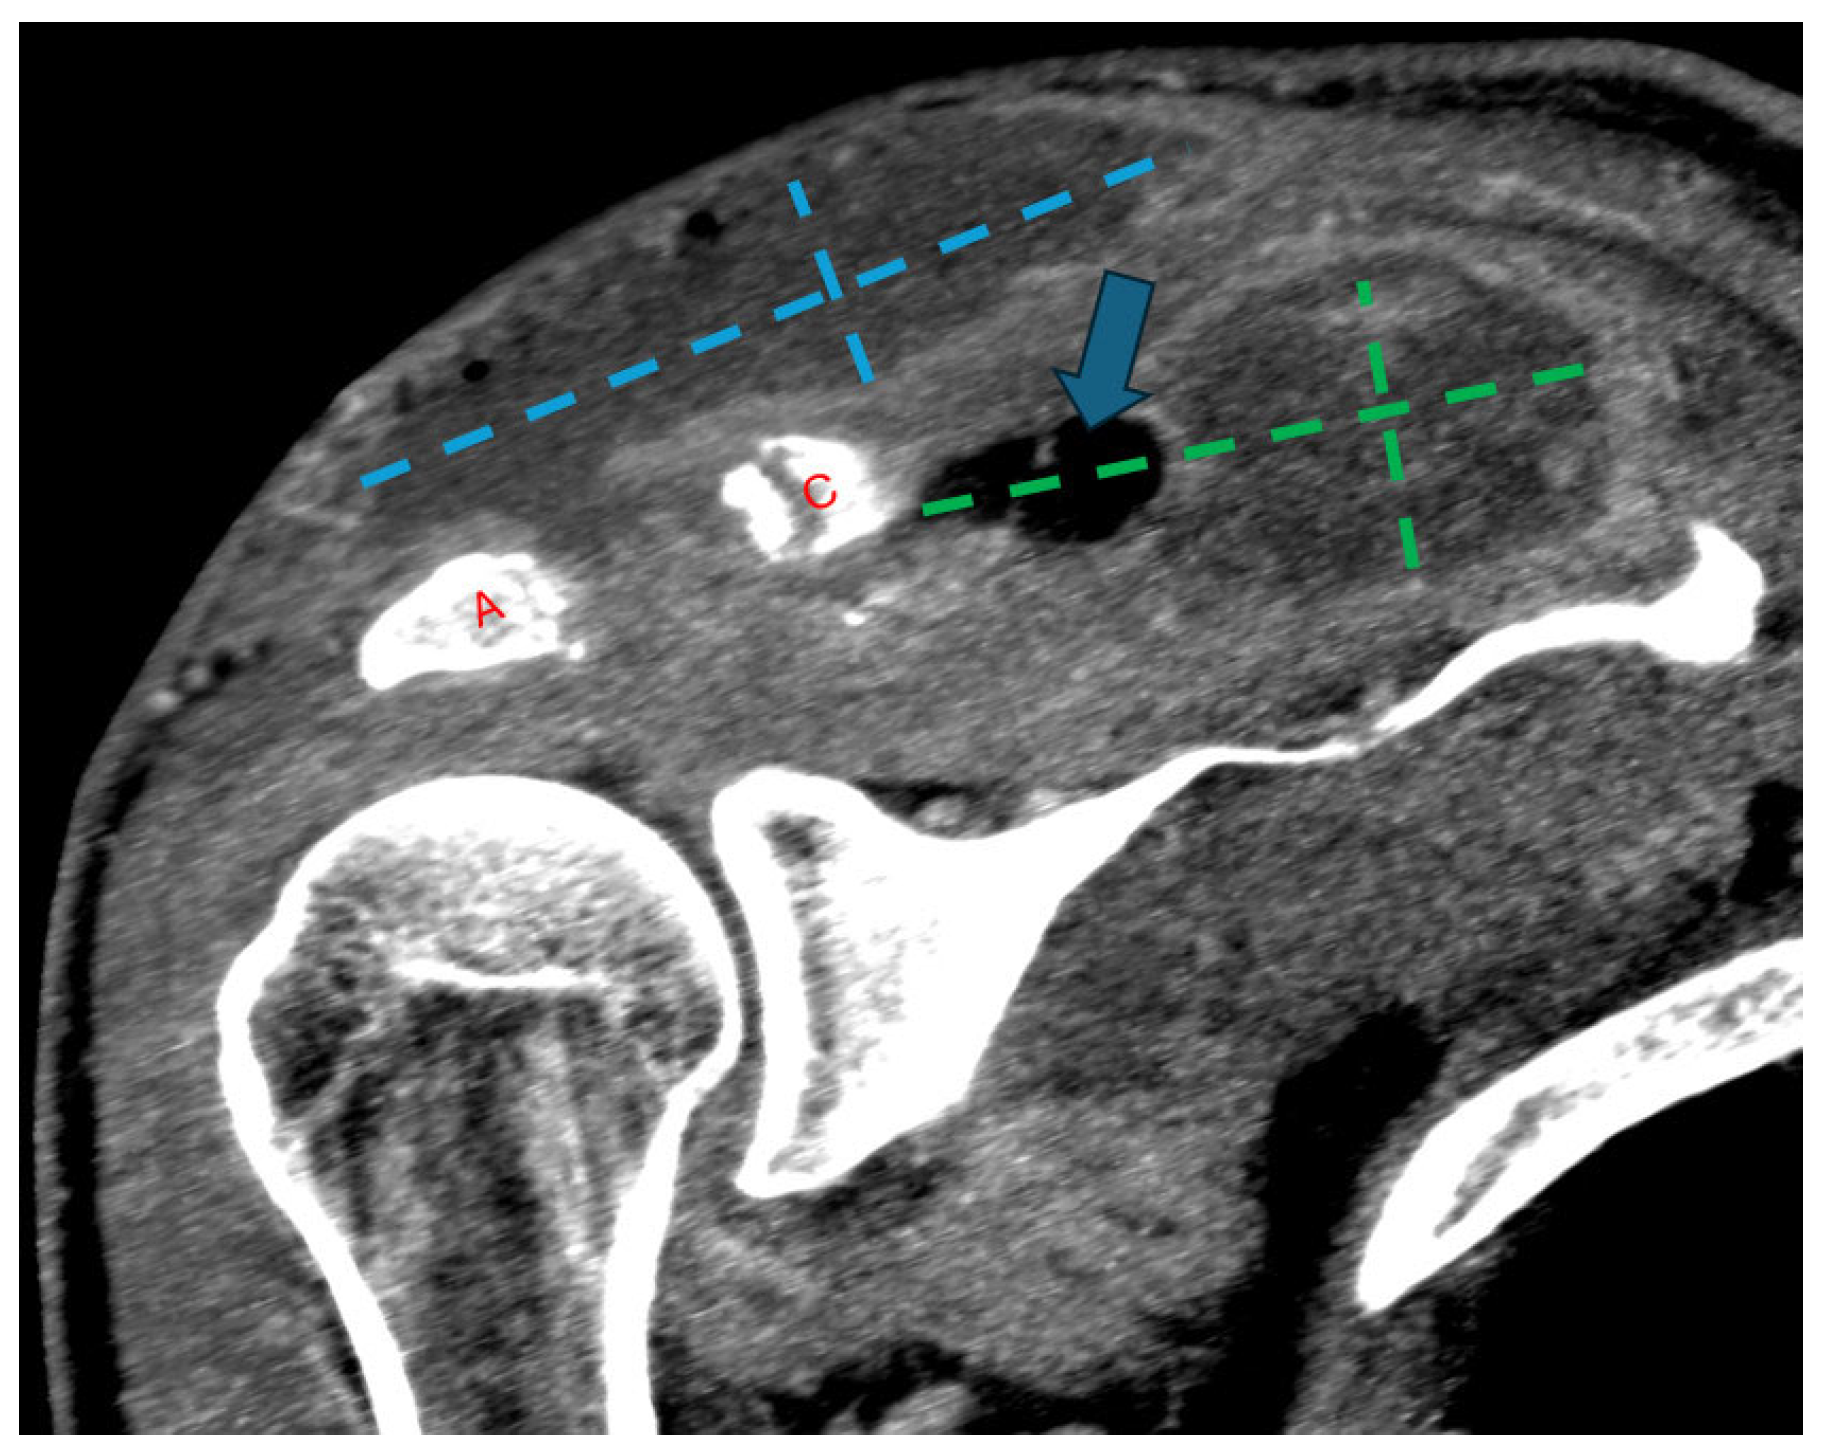

Figure 4.

Follow-up coronal computed tomography (CT) image post-contrast at the level of the AC joint (red A = acromion; red C = clavicle). Multilocular peripherally enhancing and gas-containing (blue arrow) collections have redeveloped in the superficial subcutaneous tissue directly above the AC joint (blue dashed lines) and in the supraspinatus fossa (green dashed lines). Progressive widening of the AC joint can be related to interval debridement versus progressive osteomyelitis.

He was readmitted one week later with recurrent edema and purulent drainage (Figure 3) with an elevated WBC count (10.6 × 109/L) and CRP (49 mg/L). Computed tomography (CT) with and without contrast showed extensive multifocal soft-tissue and intramuscular abscesses and progressive osteolysis of the distal clavicle and acromion (Figure 4). The following day, he underwent repeat debridement and irrigation with drain placement. Three deep tissue cultures obtained during repeat operative debridement showed no growth, likely reflecting prior antimicrobial exposure. Despite culture negativity, clinical and radiographic evidence of ongoing infection persisted, including gross purulence at reoperation, extensive multiloculated soft-tissue and intramuscular abscesses on computed tomography, and persistently elevated inflammatory markers requiring repeat surgeries. In this context, antimicrobial therapy was transitioned from ceftriaxone to 2 g of cefazolin IV every 8 h for 6 weeks to optimize musculoskeletal tissue penetration and reduce recurrence risk. At discharge, WBC was 5.7 × 109/L and CRP was 13.2 mg/L with clinical improvement. The patient was recommended home-based physical therapy for reduced range of motion and improved recovery. At 1 month follow-up post completion of antibiotic therapy, the patient was clinically well and stable without any pain, drainage, or systemic symptoms, with normalized inflammatory markers, and no evidence of recurrence.